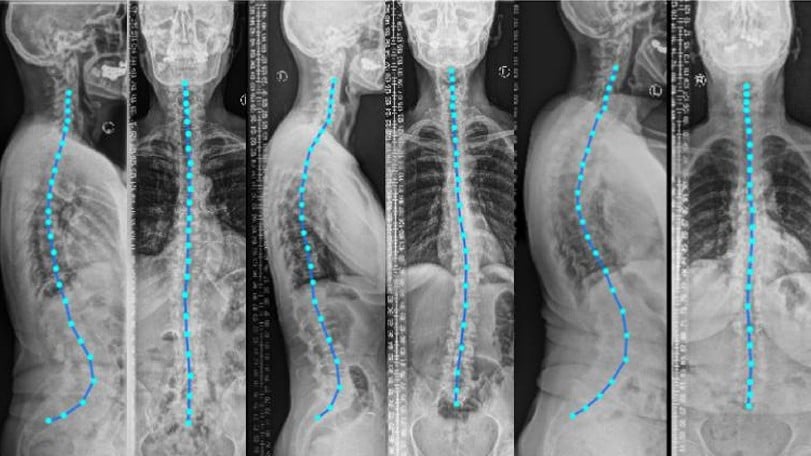

Scoliosis affects approximately 3% of the global population. Deep Learning Automation is transforming spine analysis by breaking the traditional 6-hour barrier that radiologists face when manually analyzing spinal X-rays. This time-intensive process has long been a bottleneck in diagnosis and treatment planning, especially considering the high discrepancy rates in neuroradiology, where variable readings occur in up to 21% of imaging studies.

Scoliosis detection has been markedly enhanced through deep learning applications. AI systems can identify adolescent idiopathic scoliosis (AIS) by analyzing spinal radiographs and measuring Cobb angles with impressive accuracy. In a notable advancement, deep learning models have achieved Cobb angle measurements with errors less than 3° compared to manual measurements. Through automated segmentation of ultrasonography images, these systems facilitate scoliosis diagnosis without radiation exposure—a crucial benefit for pediatric populations requiring frequent monitoring.

Deep learning automation has fundamentally changed the landscape of spine analysis, transforming a process that once took radiologists six hours into one that requires mere seconds. These AI systems now perform with remarkable precision, achieving 88% reliability in predicting spinal curvature and up to 97.9% accuracy in detecting 43 distinct spinal pathologies.

The architectural innovations behind this transformation deserve significant recognition. U-Net and ResNet architectures have achieved segmentation accuracy exceeding 88% in spinal MRI images. Vision Transformers have demonstrated 97.03% accuracy in vertebra localization, while Cascade R-CNN systems provide precise pathology detection through progressive refinement stages.